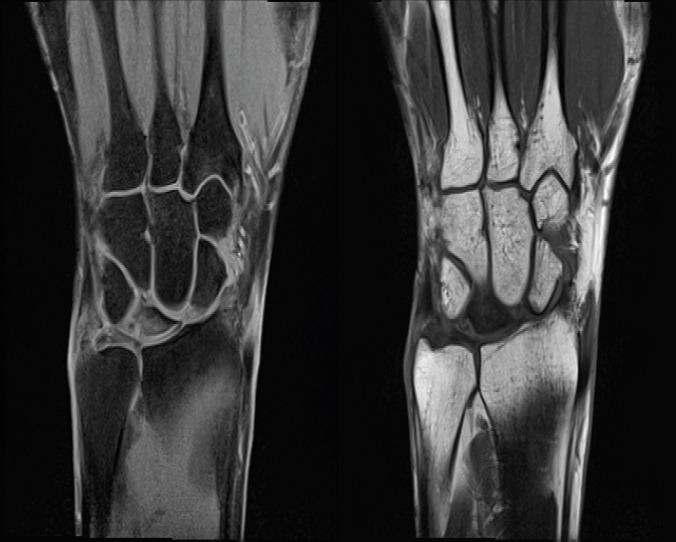

Histopathology Findings of the Lunate in Stage III Kienböck's Disease.

[Radiologic diagnosis of lunate necrosis].